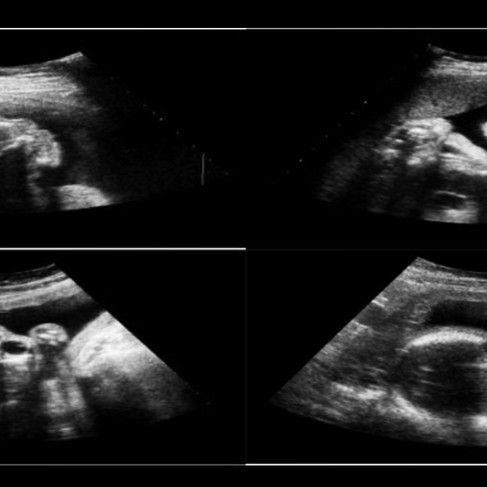

La ecografía es una técnica de imagen utilizada en medicina para obtener imágenes de estructuras corporales subcutáneas, vasos sanguíneos, articulaciones y órganos internos para excluir patologías estructurales. Esta técnica se basa en la utilización de ultrasonidos (u ondas sonoras inaudibles de alta frecuencia). En imágenes médicas, las ondas sonoras tienen una frecuencia de 2 a 18 megahercios (MHz). El equipo utiliza un transductor que actúa como emisor y receptor de ondas de sonido, y una computadora central procesa las señales eléctricas para generar la imagen. Las ventajas generales de este tipo de imágenes son su bajo costo, disponibilidad y seguridad. Algunas especialidades que dependen en gran medida de la ecografía son la cardiología, la nefrología, la cirugía general, la gastroenterología, la medicina de urgencias y la obstetricia.

Evaluacion del embarazo:

Diagnóstico

Monitoreo del crecimiento fetal